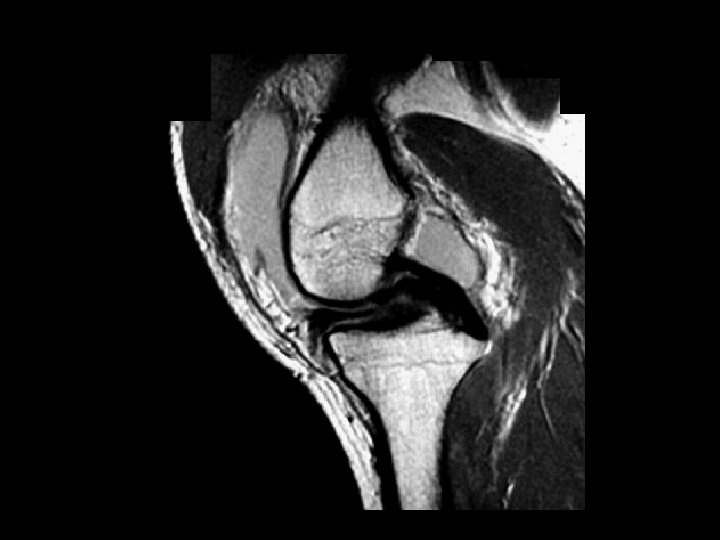

Bucket-Handle Tear • • Findings: – “double PCL sign” - torn meniscus BELOW normal PCL on sag view – Above ACL on cor view – Truncation of medial meniscus – Joint effusion Medial = 3 x lateral Locked knee ddx: – torn ACL, PCL – torn meniscus